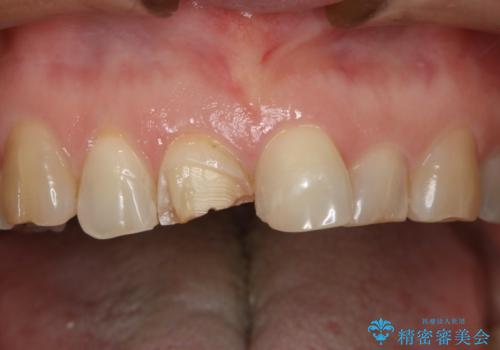

- 上顎前歯の歯冠部が破折した患者様です。神経にまでは到達していなかったので精密根管治療は行わず、審美性を考慮し、オールセラミッククラウンでの治療を選択しました。

- 121000円(オールセラミッククラウン・スタンダード)費用は治療当時の料金となります